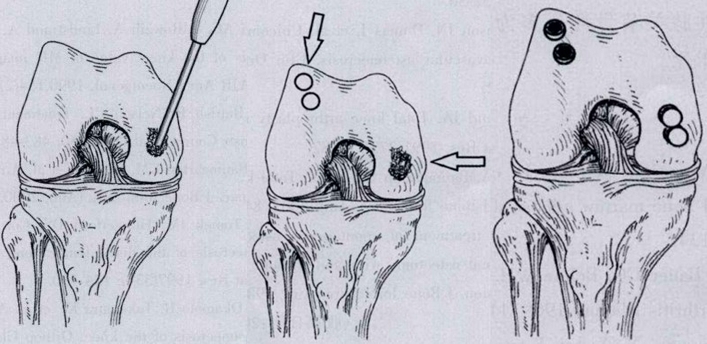

优先选择保守治疗方案,或在保守治疗方案的基础上配合行钻孔减压术,由于Koshino Ⅱ期的关节软骨仍相对完整,借助间充质细胞的重建作用及钻孔后骨内压力的降低,在该期仍可取得满意的疗效。

如果保守治疗3个月后症状没有减轻或MR上没有改善时,患者同时存在5个因素中的任一个,则应考虑行手术治疗,选择膝关节镜+自体骨软骨移植术(当患者下肢力线内翻<3°时)、膝关节镜+HTO术、或膝关节镜+HTO+坏死区病灶刮除+自体植骨术。

(3)Koshino Ⅲ期 SONK

需在考虑5个因素的基础上,同时兼顾考虑年龄、性别和活跃程度,分别选择用膝关节镜+自体骨软骨移植术(当患者下肢力线内翻<3°时)膝关节镜+HTO术+微骨折术、膝关节镜+HTO+坏死区病灶刮除+自体植骨术或单髁置换术。

行关节镜检查+软骨摘除+微骨折+HTO术,术后随访2年恢复良好,活动自如,行走时无左膝关节疼痛不适。